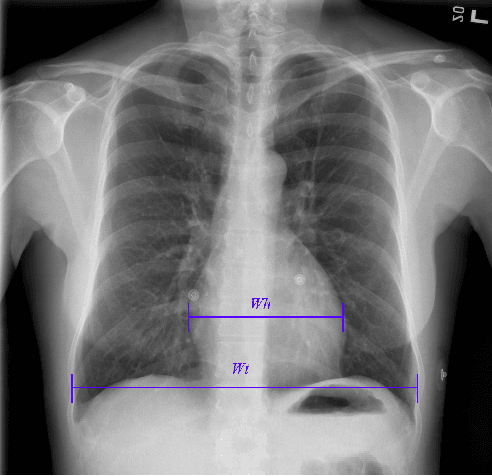

Abstract:We propose an automated method based on deep learning to compute the cardiothoracic ratio and detect the presence of cardiomegaly from chest radiographs. We develop two separate models to demarcate the heart and chest regions in an X-ray image using bounding boxes and use their outputs to calculate the cardiothoracic ratio. We obtain a sensitivity of 0.96 at a specificity of 0.81 with a mean absolute error of 0.0209 on a held-out test dataset and a sensitivity of 0.84 at a specificity of 0.97 with a mean absolute error of 0.018 on an independent dataset from a different hospital. We also compare three different segmentation model architectures for the proposed method and observe that Attention U-Net yields better results than SE-Resnext U-Net and EfficientNet U-Net. By providing a numeric measurement of the cardiothoracic ratio, we hope to mitigate human subjectivity arising out of visual assessment in the detection of cardiomegaly.